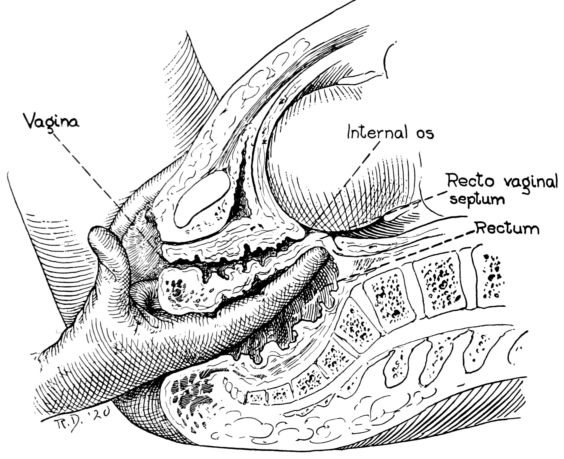

| 62. | Ascertaining position of fetus by rectal examination | 230 |